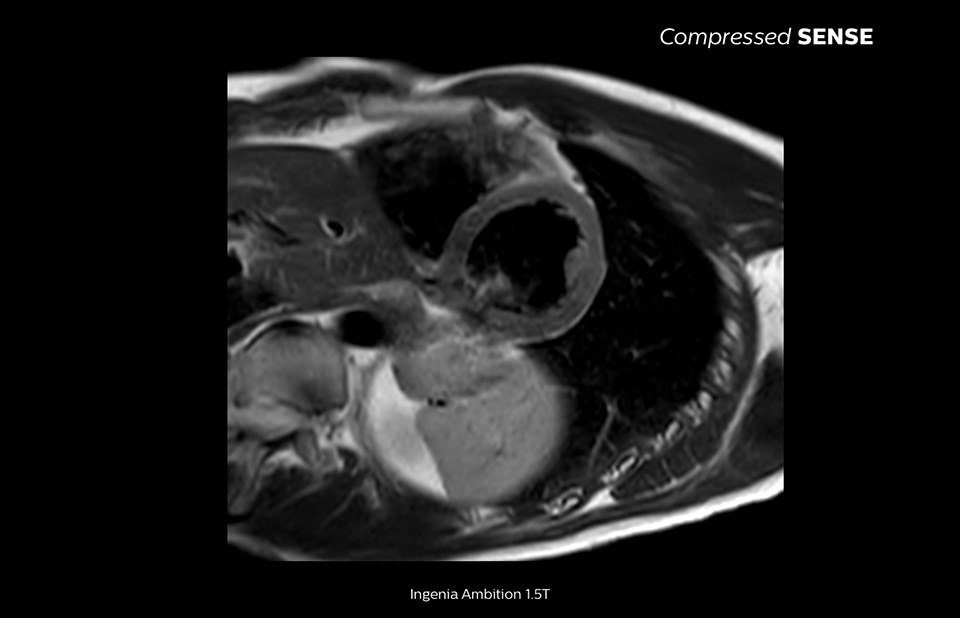

4.8 sec breath hold time

Since short breath hold times make it easier for our patients to comply, the failure of breath holding largely disappeared.

At our facility, we found in Cardiac MR fewer breath holds are now needed, or breath hold times are shortened."

Dr. Takashi Koyama, MD, PhD, Diagnostic Radiologist and Director of the Department of Radiology Center and Diagnostic Radiology, Kurashiki Central Hospital, Japan

A 15- or 16-second breath-hold is tough for many cardiac patients. With Compressed SENSE we actually have protocols now that can get that below 10 seconds. It’s a lot easier to get through for a patient, and patients are a lot more satisfied with the experience.”

Trevor Andrews, Ph.D., MR Physicist, University of Vermont Medical Center, USA